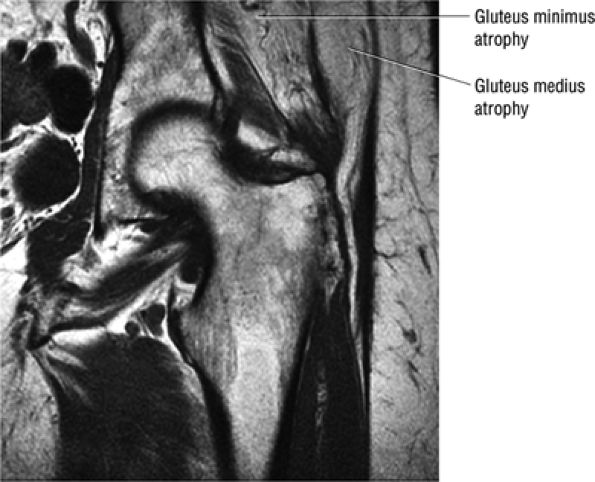

-

A defect, attenuation, or fissure in the normally intermediate-signal-intensity articular cartilage